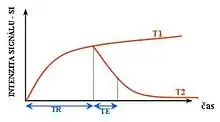

Each tissue returns to its equilibrium state after excitation by the independent relaxation processes of T1 (spin-lattice; that is, magnetization in the same direction as the static magnetic field) and T2 (spin-spin; transverse to the static magnetic field). To create a T1-weighted image, magnetization is allowed to recover before measuring the MR signal by changing the repetition time (TR). This image weighting is useful for assessing the cerebral cortex, identifying fatty tissue, characterizing focal liver lesions, and in general, obtaining morphological information, as well as for post-contrast imaging. To create a T2-weighted image, magnetization is allowed to decay before measuring the MR signal by changing the echo time (TE). This image weighting is useful for detecting edema and inflammation, revealing white matter lesions, and assessing zonal anatomy in the prostate and uterus.

Inversion recovery

Inversion recovery is an MRI sequence that provides high contrast between tissue and lesion. It can be used to provide high T1 weighted image, high T2 weighted image, and to suppress the signals from fat, blood, or cerebrospinal fluid (CSF).[40]